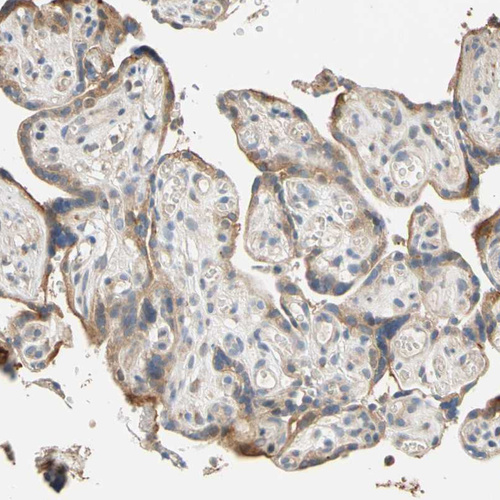

Immunohistochemical staining of human placenta shows moderate cytoplasmic positivity in trophoblastic cells.